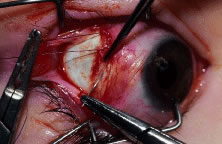

RECESSION PROCEDURE: LIMBAL APPROACH

The surgeon and the assistant sit opposing each other on either side of the patient's head. The surgical technician is located between the surgeon and the assistant.

Two 6-0 silk stay sutures are passed through the conjunctiva and superficial scleral tissue at the limbus (see Fig. 49). These sutures are used to stabilize the globe during the procedure. These stabilizing sutures attached to bulldog clamps will hold the globe in adduction or abduction as required.

A no. 15 surgical knife or other similar instrument is used to penetrate the conjunctiva at the limbus (Fig. 50). Care is taken to approach the limbustangential to the globe so that inadvertent penetration of the sclera or cornea is avoided. A Westcott scissors also may be used to incise the conjunctiva at the limbus. To facilitate this step, conjunctiva is lifted gently with a 0.5-mm Castroviejo forceps (see Fig. 50).

|

A blunt-tipped Westcott scissors is used to extend the incision for about 3 clock hours (Fig. 51). Once the fused area of conjunctiva and anterior Tenon's capsule has been penetrated, blunt dissection is performed to carry the limbal incision back toward the muscle. This maneuver is best accomplished by directing the closed tips of a blunt-tipped Westcott scissors into the tissue and letting them open to spread the tissue in a plane between the scleral surface and the underside of Tenon's tissue. The limbal incision is extended radially with a Westcott scissors (Fig. 52). Care is taken to avoid cutting into the anterior portion of the rectus muscle insertion (Fig. 53).

|

|

Figure 54 shows the conjunctiva being elevated by the assistant with Castroviejo forceps. The anterior extension of the muscle can be seen.

|

A Jameson hook is passed under the rectus muscle about 2 mm posterior to the insertion (Fig. 55). The insertion has been identified previously with a Stevens' hook that is used to lift up the tendon to facilitate passage of the Jameson hook.

Figure 56 shows sharp dissection of the intermuscular septa and the check ligaments that extend from the orbital surface of the muscle. The assistant applies gentle traction to the conjunctiva to show the surgeon the weblike bands that are to be cut. Care is taken not to penetrate the muscle capsule because penetration can injure the muscle and will cause bleeding. This dissection is carried back about 4 to 5 mm for recessions and 5 to 9 mm for resections.

A single-armed 6-0 synthetic absorbable suture is passed through the muscle tendon near its insertion (Fig. 57). A double-lock bite is taken with the needle, and the suture is tied with two square knots to secure it to the upper and lower poles of the tendon of the rectus muscle. The muscle is lifted or tented off of the surface of the globe with a Jameson hook. A Westcott scissors is used to cut the muscle free (Fig. 58).

|

|

The assistant holds the Castroviejo caliper that marks the location of the new insertion (Fig. 59). Care is taken to locate it directly posterior to the stump of the old insertion and to avoid inadvertent supraplacement or infraplacement of the new insertion.

|

An intrascleral passage of the needle is used to secure the muscle to the globe (Fig. 60). The intrascleral bites are usually 3 to 4 mm in length. The superior and inferior pole sutures are tied to secure the muscle to its new insertion site (Fig. 61), and the wound is inspected. The new insertion is measured to ensure that the appropriate amount of recession effect has been achieved. The sutures are trimmed, and the conjunctiva is brought back to the limbus (Fig. 62). Care is taken to identify the conjunctival tissue. Confusion may occur when an attempt is made to differentiate this tissue from Tenon's tissue. A fine absorbable suture such as 8-0 collagen is used to secure the conjunctiva at the limbus (Fig. 63). If an en bloc recession technique is used, or a bare sclera closure is required, the conjunctiva is recessed 4 to 5 mm back from the limbus, leaving the sclera between the anterior conjunctiva edge and the limbus uncovered. This technique is useful when conjunctival and subconjunctival tissue is contracted or when it restricts movement of the globe.

|

|

|

|